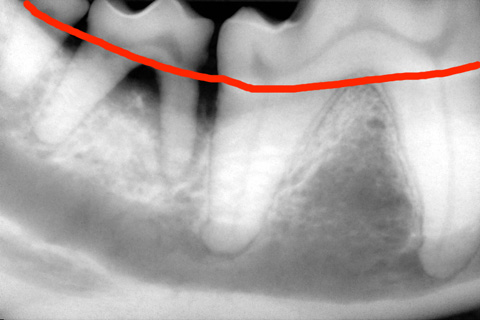

その2(重度の所見)

歯のレントゲン写真

歯を支える骨が腐って溶けています。歯が浮いています。

赤い線がハグキの線です。まもなく下アゴの骨が骨折する可能性があります。